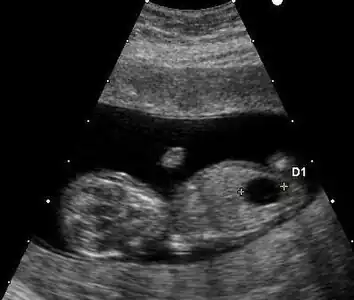

Ultrasound

Prenatal ultrasound can be used to screen for Down syndrome. Findings that indicate increased chances when seen at 14 to 24 weeks of gestation include a small or no nasal bone, large ventricles, nuchal fold thickness, and an abnormal right subclavian artery, among others.[113] The presence or absence of many markers is more accurate.[113] Increased fetal nuchal translucency (NT) indicates an increased possibility of Down syndrome picking up 75–80% of cases and being falsely positive in 6%.[114]